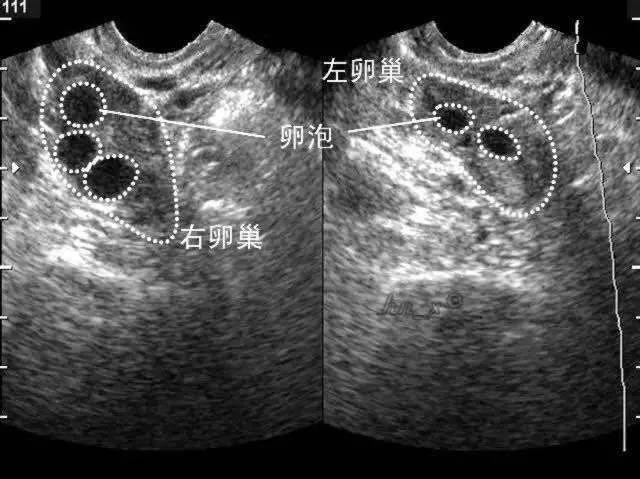

众所周知,正常育龄女性每个月经周期会排出一个成熟的优势卵泡,以备受孕,可以说卵泡发育质量决定生育质量。在试管婴儿助孕过程中,影响试管婴儿成功率的一个重要因素就是获得优质的卵子,因此,PACCLINIC专家会在促排卵期间对卵泡进行监测。

卵泡是在卵巢皮质内由一个卵母细胞和其周围许多小型卵泡细胞所组成。根据卵泡发育过程的形态和功能变化,可分为原始卵泡、生长卵泡和成熟卵泡三个阶段。“卵巢”最主要的功能是产生“卵子”,卵子在卵泡里和卵泡同步成熟,发育良好的卵子是试管婴儿成功的保证。但是卵子太小,肉眼看不见,在试管婴儿中,为了成功取到优质的卵子配成胚胎,只能间接地通过观察卵泡来推测卵子的发育情况。卵泡发育最简单、最直观的评估是通过超声观察,每个周期通过3-4次的超声监测,可以观察到有没有正常的卵泡生长、发育、以及何时可进行取卵手术。

在试管婴儿超促排卵过程中,卵泡监测是为了评价卵巢刺激的效果与决定取卵的时间。当两个以上卵泡直径大于18mm,便可当日“打夜针”注射人绒毛促性腺激素(HCG),促使卵泡成熟。在注射HCG后36小时取卵。成熟卵泡圆而饱满,内壁薄而清晰,有张力。卵泡数量过多,要警惕卵巢过度刺激综合征的发生。每个人对促排卵药的反应也不一样,有的人卵泡前期长得慢,也不用过于担心,医生也会根据个人情况不同调整药物的。